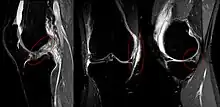

The unhappy triad, also known as a blown knee among other names, is an injury to the anterior cruciate ligament, medial collateral ligament, and meniscus. Analysis during the 1990s indicated that this 'classic' O'Donoghue triad is actually an unusual clinical entity among athletes with knee injuries. Some authors mistakenly believe that in this type of injury, "combined anterior cruciate and medial collateral ligament (ACL- MCL) disruptions that were incurred during athletic endeavors" always present with concomitant medial meniscus injury. However, the 1990 analysis showed that lateral meniscus tears are more common than medial meniscus tears in conjunction with sprains of the ACL.[1]